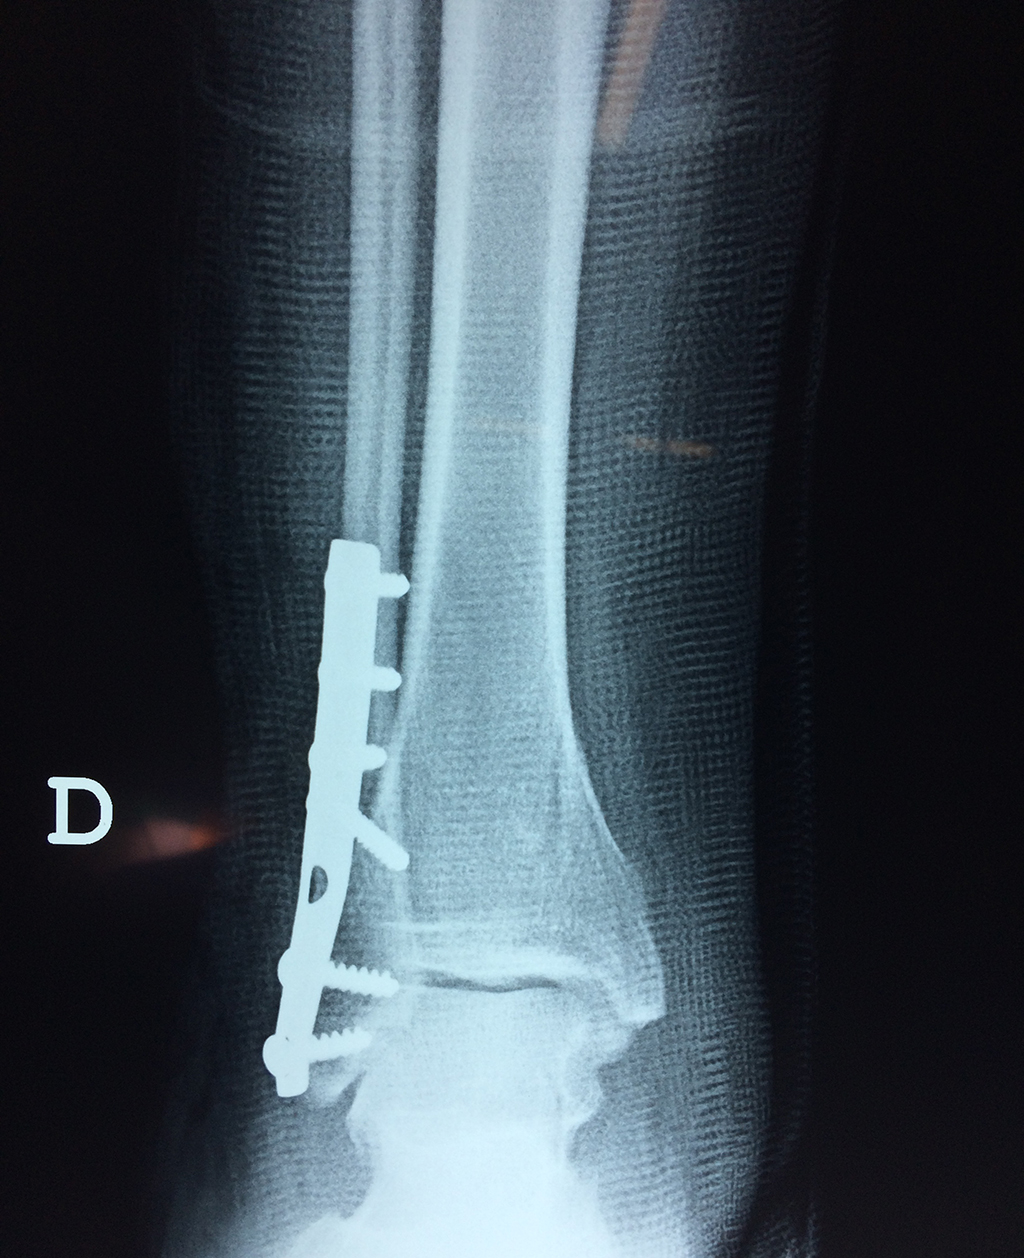

Cuando se necesita cirugía, es probable que esta implique el uso de clavijas de metal, tornillos o placas para sostener los huesos en su lugar mientras la fractura se consolida. Los elementos de soporte pueden ser temporales o permanentes.